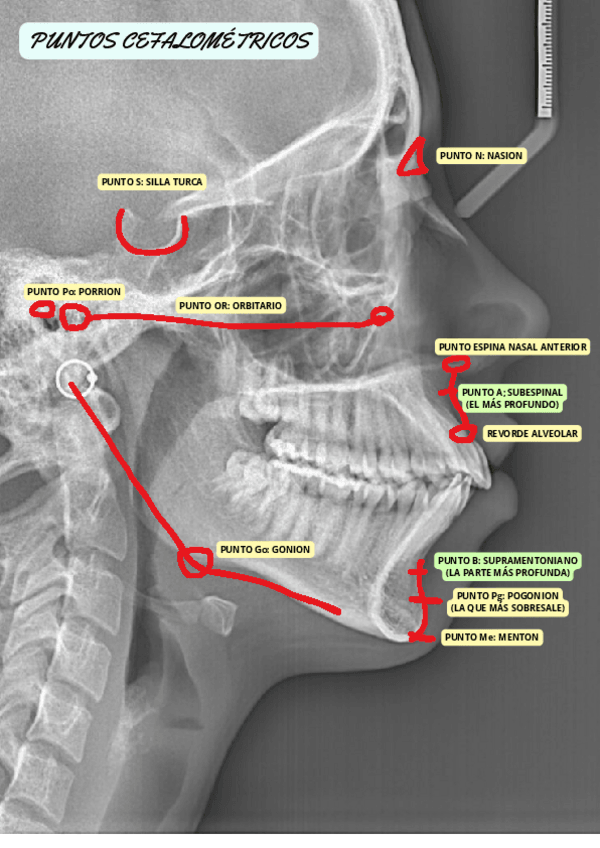

PUNTOS-CEFALOMETRICOS-Y-ANALISIS-DE-STEINER-T10-PROTESIS.pdf